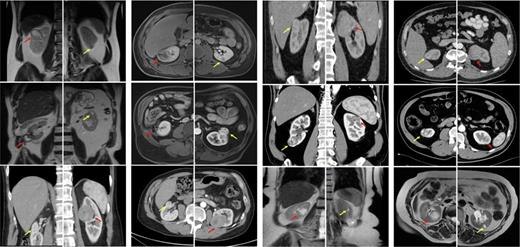

Each patient received OPN on one side and RAPN on the contralateral side. Representative images of all the tumors are shown in Figure 1. The median age was 65 (55–75) years and the cohort included 1 female (17%). The median body mass index was 27 (23.4–30.2) kg/m2 and the median abdominal circumference was 93.7 (87.6–103.6) cm. The time between the two surgeries was 1.8 (1.3–7.2) months, with OPN performed before RAPN in all patients. One major complication (Clavien-Dindo 3) occurred in the OPN group, and none occurred in the RAPN group. One patient treated with OPN for a RENAL 8p kidney tumor experienced postoperative urinoma. After insufficient clinical improvement after drainage, ureteral stenting, and i.v.-antibiotics, revision surgery was performed. Tumors with greater complexity were more often treated with OPN (median RENAL score OPN 8 vs. 6 RAPN). This aligns with our surgical strategy of treating more complex tumors first, typically with OPN, to ensure nephron-sparing. In 2 patients with identical RENAL scores for both sides (8a and 8p), the decision for the surgical strategy was made based on the complexity-by-score, individual preference, and other patient-specific anatomical considerations. Hospitalization duration was longer after OPN (7 days) vs. RAPN (5 days) and ischemia time for OPN was 10 min vs. 5 min for RAPN. There was no difference in the dynamics of postoperative kidney function between the two cohorts. The predominant histologic subtype was clear-cell renal cell carcinoma. There was a greater proportion of T1b tumors in the OPN group; the RAPN group consisted solely of T1a tumors. No patients had a positive nodal status or distant metastases. The surgical and oncologic characteristics of our cohort are shown in Table 1.

CT/MRI scans of all patients in the cohort. The red arrows indicate the tumors treated with OPN, and the yellow arrows indicate the tumors treated with RAPN.